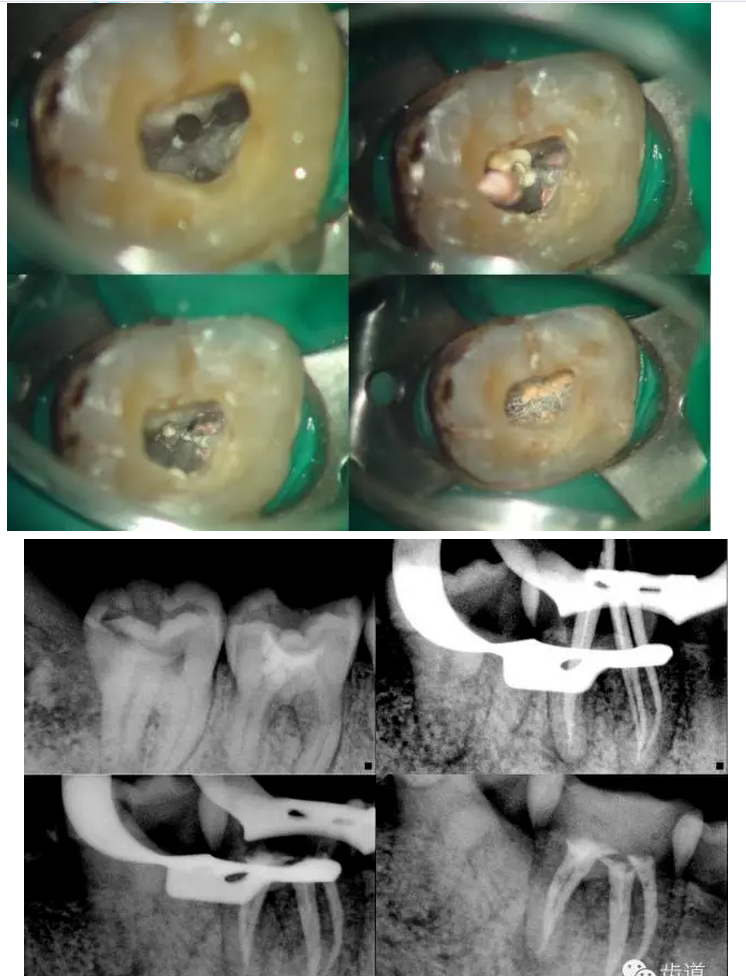

鄭玉琪:尋找迷失的根管第二季——容易遺漏的根管

上頜第一磨牙:多為3-4個根管,MB2發(fā)生率約為60%;

下頜第一磨牙:為3-4個根管,遠(yuǎn)中雙根管的發(fā)生率為51.4% 左右,側(cè)支根管發(fā)生率為30%左右;